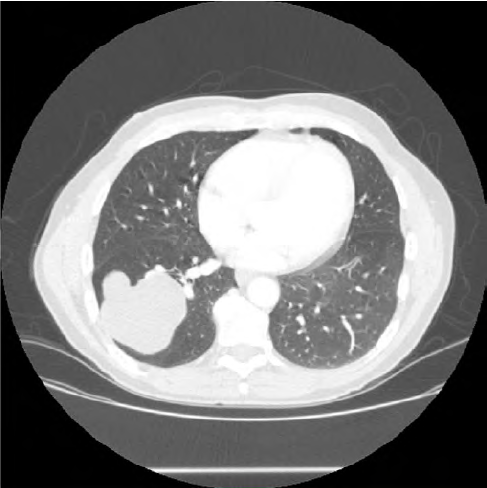

Se solicita una radiografía de tórax preferente desde Atención Primaria con fecha 14/04/15. El paciente acude a recoger el resultado el 20 de abril (figura 1). A la vista de las múltiples lesiones redondeadas de gran tamaño se contacta vía telefónica con el servicio de Urgencias del Hospital General de Villarrobledo, que solicita TAC abdominopélvico con contraste intravenoso y analítica completa; ambos se realizan el día siguiente. Al mismo tiempo contactan con el Servicio de Neumología, que realiza una espirometría ese mismo día y cita para una fibrobroncoscopia en menos de una semana (el 27 de abril).

Resultado del TAC toracoabdominal con contraste intravenoso (figura 2): masas quísticas de 67 y 75 mm de diámetro uniloculares polilobuladas en lóbulo inferior derecho; como primera posibilidad diagnóstica hidatidosis pulmonar.